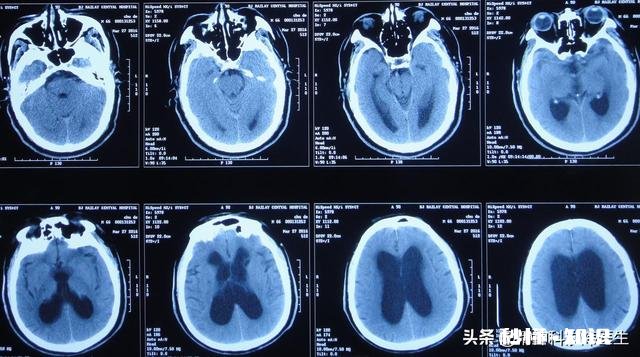

感请,你的问题很好,也是我增加困惑的一个问题 。不过还是得益于科学的进步 , 我们现在可以肯定的说精神分裂症每犯一次都会伤害一次大脑,是很有可能的事情,虽然目前的医学没办法找到准确的证据,但是现有的影像学检查还是支持这个结论的 。

文章插图

关于精神分裂症的脑结构变化记得十多年前,刚参加工作的时候 , 我们还在说:精神分裂症是一种功能性疾病,不存在器质性改变,这样的观点统治了全世界精神医学领域数十年 。但目前的医学影像学技术不断进步不断进步,我们还是很确切的找到了长时间精神分裂症患者的脑部结构变化的证据 。

并且,熟悉精神分裂症的人都知道 , 精神分裂症患者往往每复发一次治疗一次,下次再复发的时候就会变得更加难以治疗,很多时候可能需要增加药物治疗剂量,甚至更换治疗药物或者联合第二种抗精神病药物才能有效缓解 , 所以我们说,精神分裂症是一种慢性病程,进行性加重的精神障碍,那既然脑影像已经证明,精神分裂症的脑结构会逐渐发生变化 , 当然会表现为每次发作都会加重上一次的脑部结构变化,也就是题主说的——精神分裂症每犯一次都会伤害一次大脑 。

虽然精神分裂症的发病原因尚不明确 , 但通过对精神分裂症个体的检查发现:部分精神分裂症患者出现大脑结构异常,包括脑层萎缩、脑室扩大等异常状况等,这提示可能与脑组织发育受阻有关。